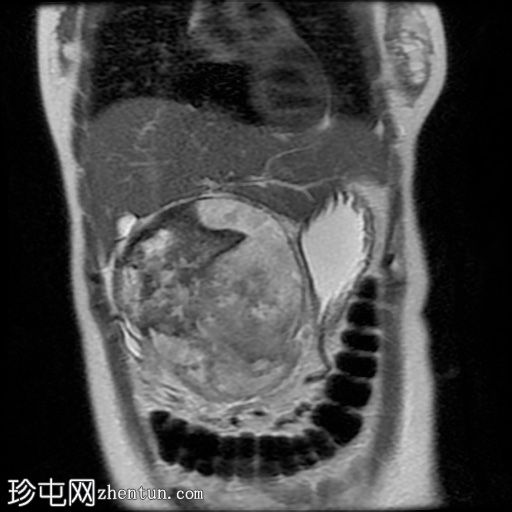

MRI

冠状位

5.jpg

T2加权像

冠状位T2加权像

6.jpg

脂肪抑制像

7.jpg

MRCP

病灶在T2加权像上呈不均匀高信号,内部区域信号强度不一。

MRCP显示胆总管正常,无胆管扩张或梗阻征象。

主胰管未见,可能由于肿块压迫/取代所致。